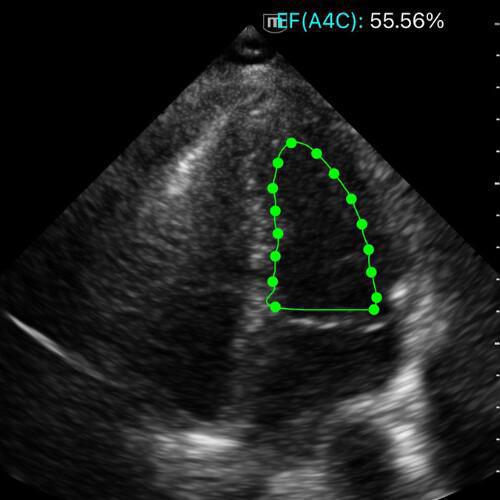

Apicale quatre cavités → estimation visuelle FEVG, calcul en méthode Simpson, MAPSE, onde S'

👀 Méthode visuelle

Observer la variation de volume du VG entre diastole et systole, et la vitesse du rapprochement des parois.

Un VG normal diminue d’environ un tiers de son diamètre à chaque battement :

- les parois se rapprochent harmonieusement,

- la cavité se vide presque complètement,

- le mouvement est vif et synchrone.

Quand la fonction baisse, la contraction devient lente, inégale, le VG reste dilaté, la valve mitrale s’ouvre peu et le volume résiduel systolique augmente.

Trois profils suffisent à la décision :

- Normale : cavité qui se vide franchement, parois toniques.

- Diminuée : contraction lente, cavité résiduelle importante.

- Très diminuée : parois quasi immobiles, volume constant.

Vue A5C avec FEVG normale.

Vue A4C avec FEVG diminuée.

Vue A4C avec FEVG très diminuée.